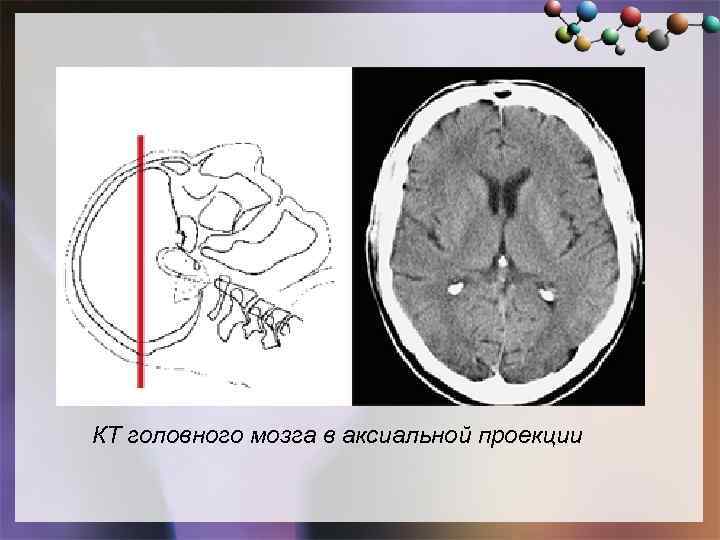

КТ головного мозга в аксиальной проекции

КТ головного мозга в аксиальной проекции